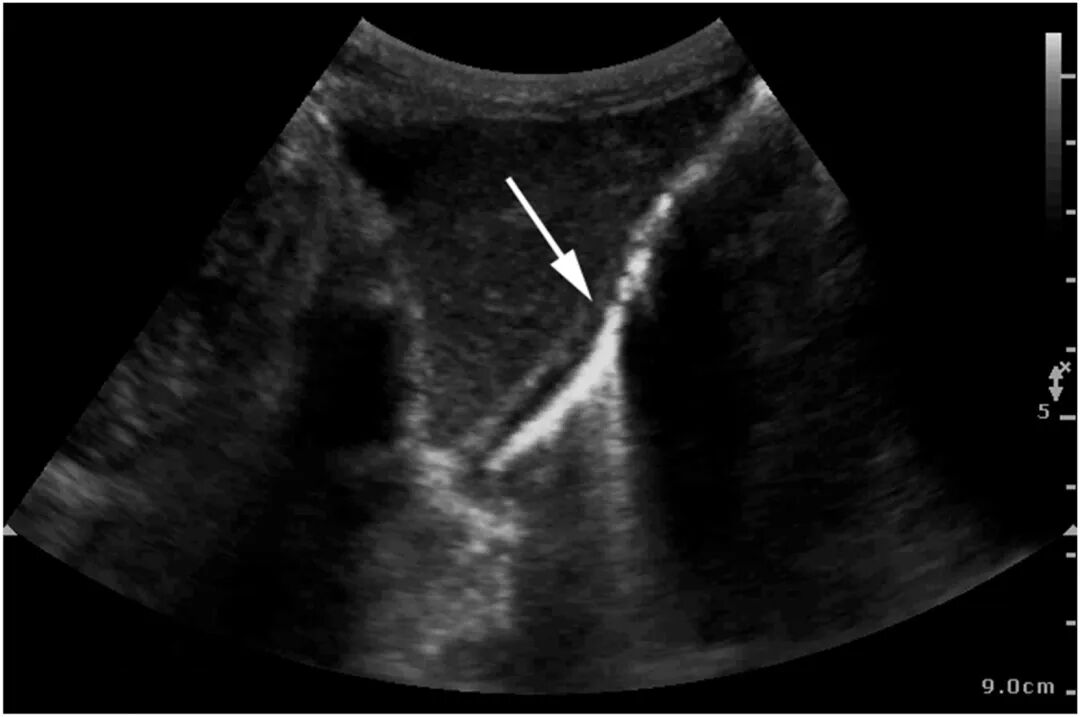

图2 床旁超声剑突下切面显示胃壁"彗星尾"伪影

图3 床旁超声左肋间切面显示胃壁"彗星尾"伪影(箭头)